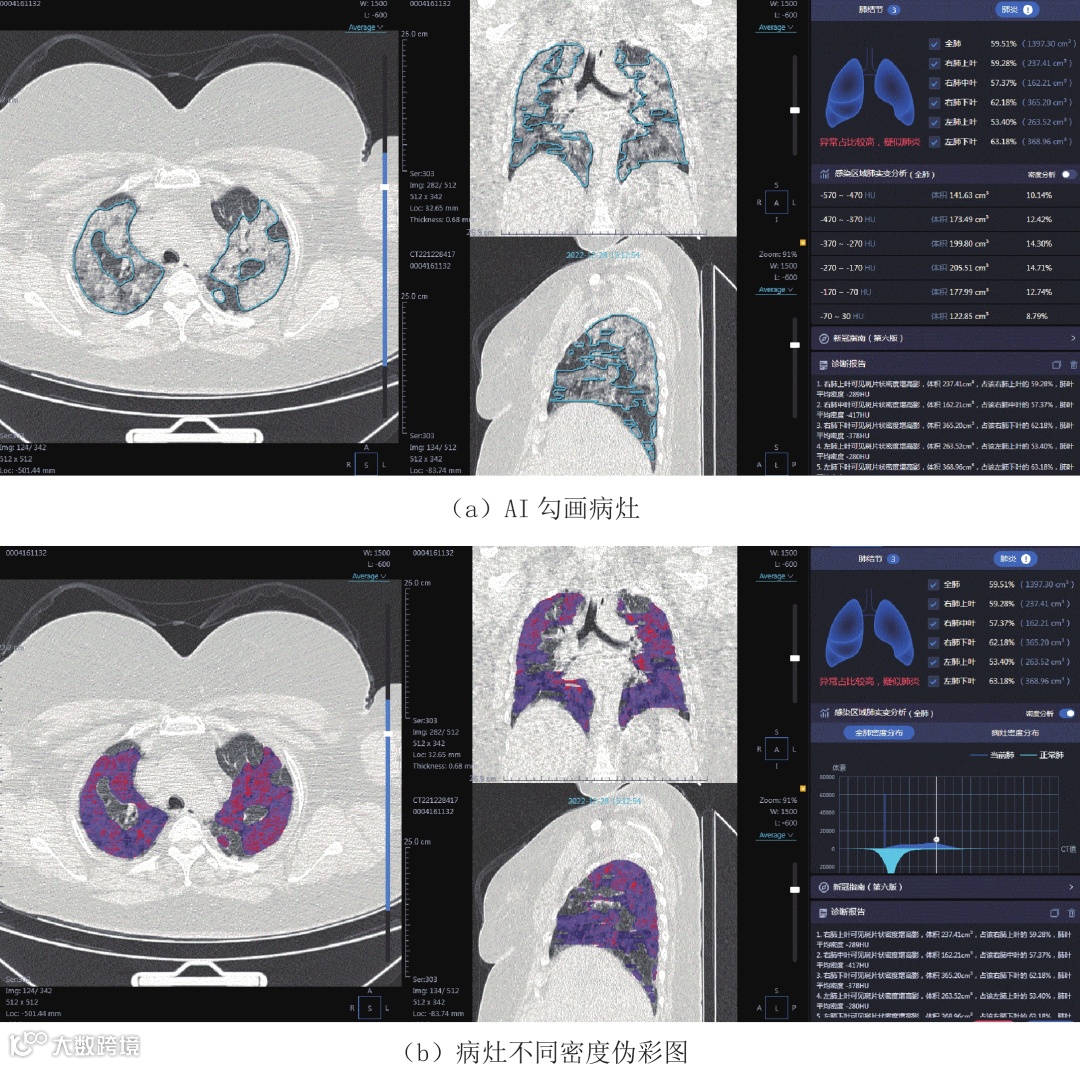

肺结节检测是医疗影像AI最为成熟的应用领域之一。肺癌是全球致死率最高的恶性肿瘤,低剂量CT(LDCT)作为早期筛查手段已被广泛推荐。然而,放射科医生在面对海量薄层CT图像时容易出现视觉疲劳,导致微小结节(<6mm)漏诊率高达15%-20%。Qwen系统通过构建多尺度3D卷积神经网络,结合U-Net++分割架构与SE注意力模块,实现了对肺实质内孤立性或簇状结节的自动定位与定性分析-6。该流程分为三个阶段:图像预处理采用基于LungSegNet的肺野自动分割算法提取感兴趣区域(ROI),去除气管、骨骼等干扰结构;候选结节检测使用Faster R-CNN变体进行初始定位;分类与风险评估集成ResNeXt-3D骨干网络,结合临床信息输出良性/恶性概率评分。某省级胸科医院的部署数据显示,引入AI辅助后,平均每例CT阅片时间从12.4分钟降至7.1分钟(↓42.7%),<6mm微小结节的检出率从68.3%提升至89.6%(↑31.2%),同时假阳性率降低了31%。